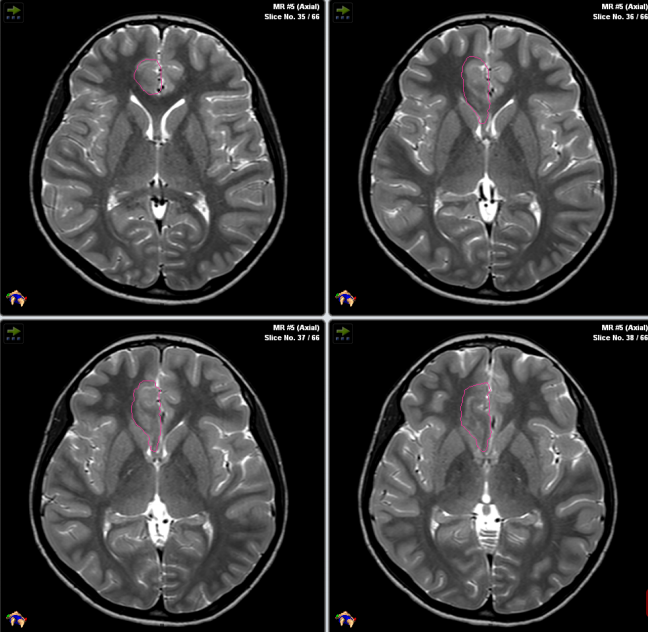

案例3:局灶性皮质发育不良

Rutka在INC中国年会上曾分享过这样一则案例:一名患有额叶癫痫的12岁男孩,伴有运动机能亢进的癫痫发作,神经成像检查结果显示:右侧额内侧下基底病变,他接受了开颅右额叶病灶切除术,病理资料显示为局灶性皮质发育不良(FCD),术后三个月无癫痫发作。

不幸的是,三个月后他的癫痫复发了,但Rutka教授不希望孩子在短时间内再次接受开颅手术,因此与患者家属深入沟通后决定为其进行激光间质热疗。

Rutka教授和他的团队正在为其手术

术后他便没有癫痫发作了,而且近期随访显示其生长发育和智力发育正常,而且癫痫并未复发。